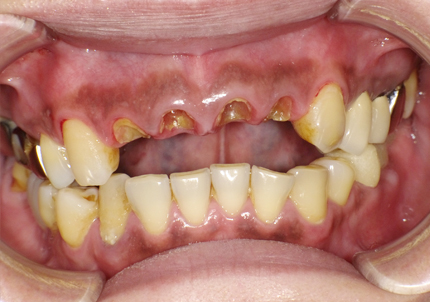

1.初診時口腔内写真(2014年6月)

主訴 :義歯が嫌いで使わず奥歯が咬めないので、全体の治療を希望する

治療計画 :

・上顎補綴物再製

・右下2本インプラント

・左下ジルコニアクラウンブリッジ